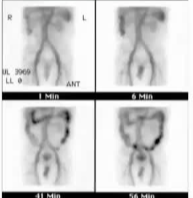

·Scintigraphy(核素显像)

o 即红细胞闪烁显像(tagged RBC scan),敏感度高但定位精度较低

o 适用于间歇性出血、血流动力学稳定的患者

o 若阳性,可为后续血管造影或手术提供定位依据

核医学显像